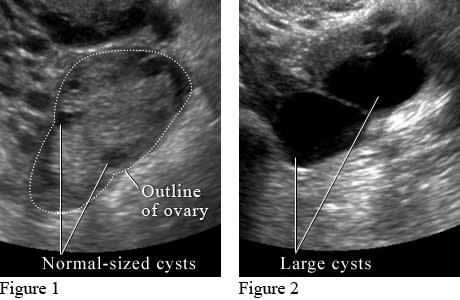

What do ovarian cysts look like on ultrasound?

Figure 1 shows small normal-sized cysts. Figure 2 shows large cysts that affect the ovary and may cause pain.

Image courtesy of Intermountain Medical Imaging, Boise, Idaho.